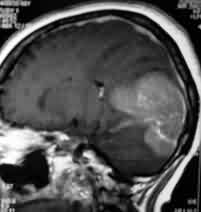

|

Bifalcine

meningioma-MRI

|

Falx meningioma-MRI